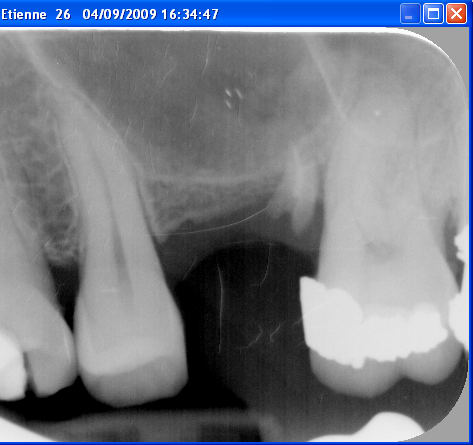

Le cas date de 2010, le sinus est traité par élévation crestale + mise en place de 2 mb de PRF dans le "trou" avant de combler au RTR et en dernier os récupéré du forage pour espérer qu'il reste contre l'implant.

J'ai pas pu enlever le prénom mais vous avez les dates dans l'ordre

La radio postée hier est un "contrôle à 6 ans avant d'implanter en 14

Petite question qui n'a rien avoir avec le sujet :-)

Qu'est-il arrivé à la 23? Elle présentait un soin mal adapté en 2009, puis a été couronnée en 2010, et aujourd'hui, plus rien, disparue...

29/04/2016 à 17h36

pour carident

comme tu le vois sur la première radio du premier post, elle va bien avec un composite distal